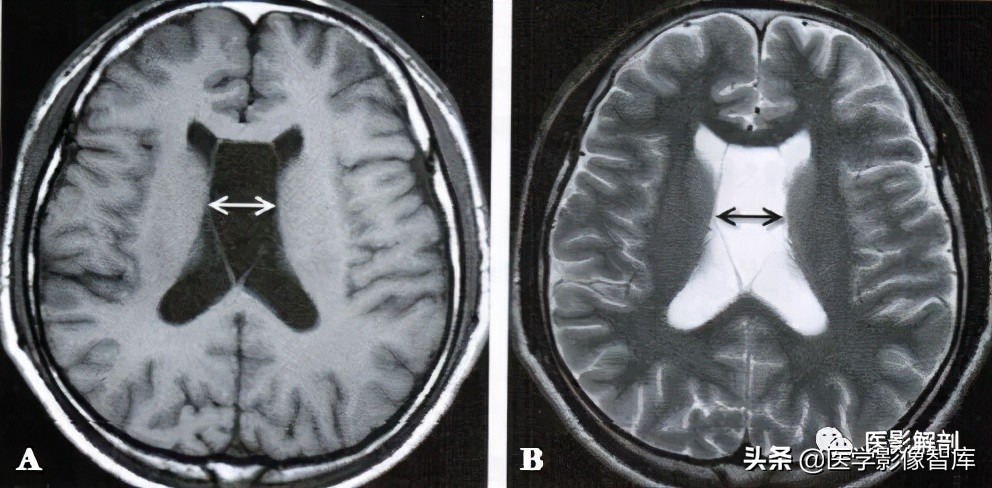

图1 第五脑室

男性,58岁。A.轴面T2WI,B.轴面T2WI。双侧的透明隔未融合,其内充满长T1、长T2脑脊液信号形(箭)。

在轴面MRI上,透明隔间腔出现在第三脑室上部层面的图像上,位于两侧侧脑室额角之间,其内为脑脊液信号,可呈条带状、三角形或类似梯形,边缘清楚,两侧壁多平行,向后直抵侧脑室室间孔(图1)。位于透明隔两侧壁之间的腔隙宽度至少要>1mm且<10mm,才可称其为透明隔间腔。